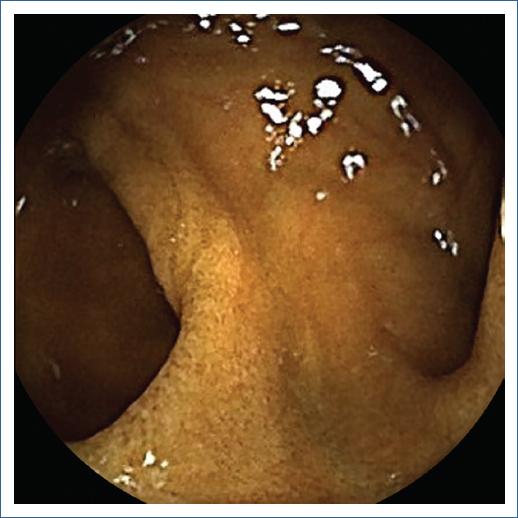

A 29 year-old woman with a medical history of hemorrhoids without any other chronic diseases presented with a 6 years history of painless hematochezia. A colonoscopy was performed, reporting ileal nodular hyperplasia, a hyperplastic polyp and isolated erythema patches of mucosa in her sigmoid and internal hemorrhoids. Four months prior to her evaluation she reported intermitent pain in her meso and hipogastrium. An upper endoscopy was perfomed, reporting a grade B erosive esophagitis and antral eritematous gastropathy. Capsule endoscopy (Figure 1) showed a small erosion and a double-lumen sign in the ileum, consistent with a diverticulum, with no signs of active or recent bleeding. A Meckel´ scan (Figure 2) was peformed, with no evidence of ectopic gastric mucosa. Due to persistence of symptoms, she underwent a exploratory laparoscopy (Figure 3); a Meckel´s diverticulum (MD) was found and removed 80 cm proximal to the ileocecal valve. Histologic evaluation showing gastric mucosa confirmed MD. The patient had an adequate post-surgical evolution. She was followed up for 6 months without recurrence of symptoms.

Figure 1 “Double-lumen” sign on capsule endoscopy, suggestive of small intestine diverticulum.